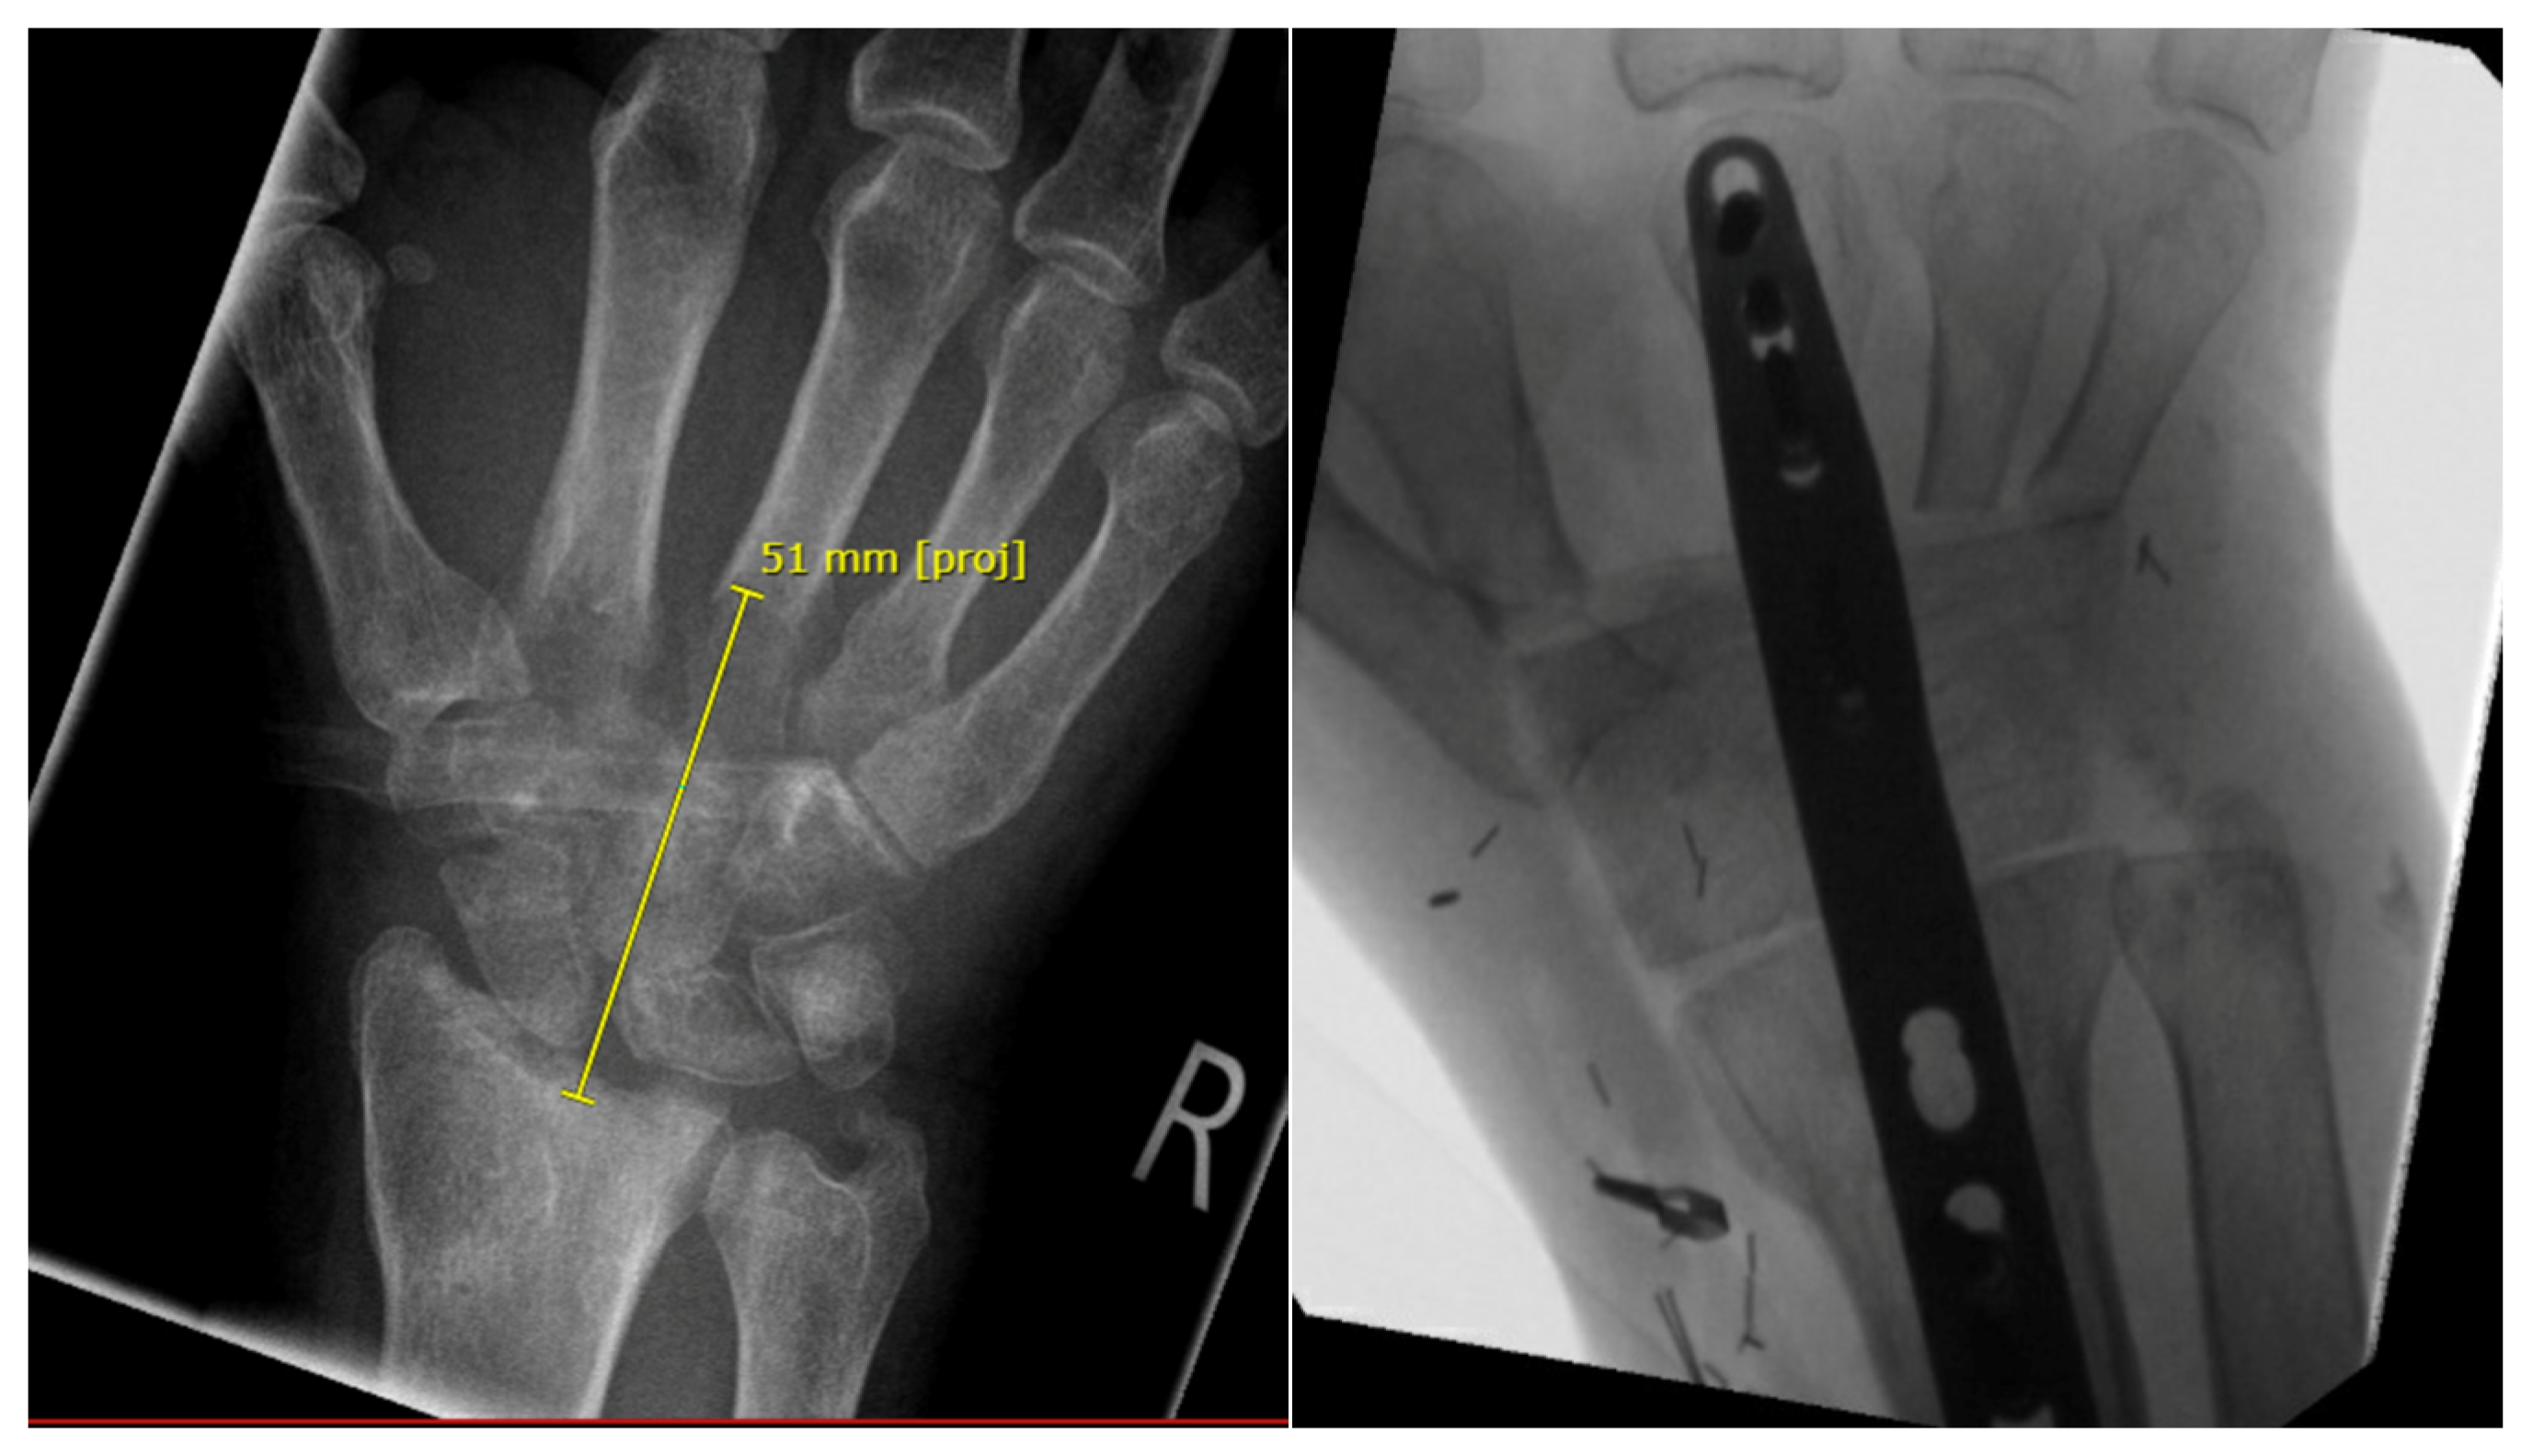

3.2.2. Arthrodesis of the Distal Radius and Middle Hand Using a Triangular-Shaped Vascularized Osteocutaneous Fibula Flap

| Case 3 | Complete wrist, distal radius and proximal metacarpals | Benign, aggressive bone tumor | 53 | 41 | 8 cm | Vascularized osteocutaneous triangular fibula | Wrist arthrodesis | N/A N/A | 0-0-0° 80-0-40° | 70% | MMWS = 45 DASH = 30 | yes | |